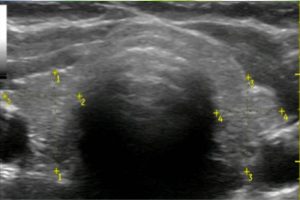

Diplomados en Ultrasonografía